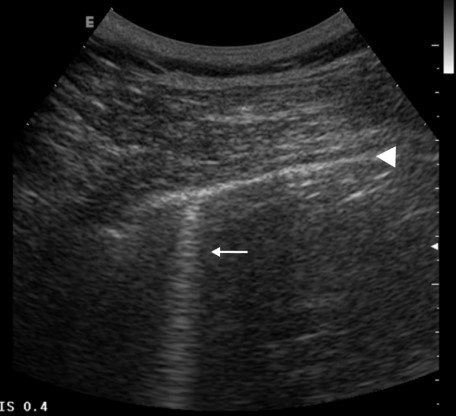

Al existir aire entre las dos pleuras éstas dejan de estar en contacto entre sí. Por lo tanto, un signo de la presencia de neumotórax consistirá en que no hay lung sliding en la zona explorada. Al explorarse en el modo M, observaremos que se pierde el signo de la playa, y en su lugar es reemplazado por el signo de la estratósfera o del código de barras (figura 3).

Un signo no tan sensible como el anterior, pero 100% específico de neumotórax es la presencia del punto pulmonar (figura 4). Se observa la zona precisa en que deja de haber lung sliding, y en el modo M, la zona precisa donde la “playa” pasa a ser el “código de barras”.

Resumen de síndrome de neumotórax: Ausencia de lung sliding, ausencia de líneas B, presencia del signo de la estratósfera, presencia de lung point.

| Signo de la estratósfera (o del código de barras) | Imagen en modo M donde solo se visualizan líneas horizontales paralelas (se pierde la orilla de playa). Indica neumotórax. |

| Signo del punto pulmonar (lung point) | Punto donde se separa el deslizamiento pulmonar de la ausencia de éste. En modo M se ve un punto de cambio de imágenes normales (arena de playa) a imágenes anormales (estratósfera). Patognomónico de neumotórax. |